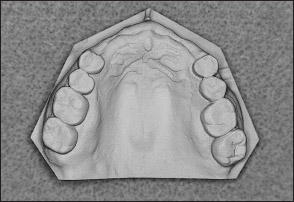

• Kennedy Class I arch: Characterized by bilateral edentulous areas located posterior to the remaining natural teeth (Figs 1-11 and 1-12).

Fig 1-11 Maxillary Kennedy Class I arch.